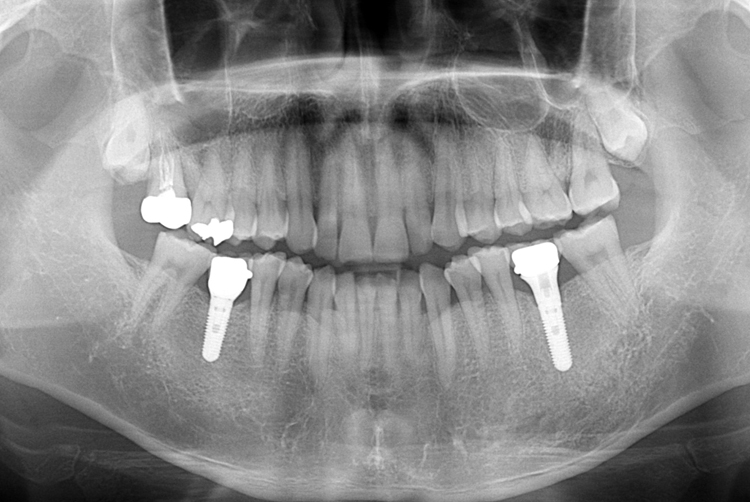

치료후 : 2019-05-09

세종치과는 많은 환자와 다양한 케이스를 바탕으로

항상 편안한 임플란트 수술을 제공하고자 노력하고,

오래동안 튼튼히 쓸 수 있는 임플란트 수술을 가장 큰 목표로 삼고 있습니다.